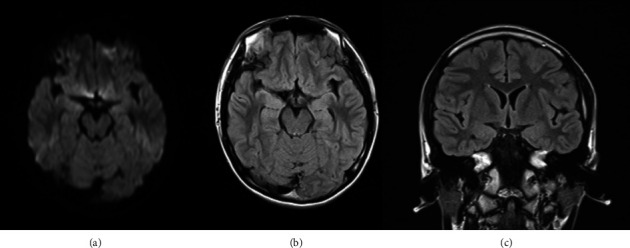

Abstract Image